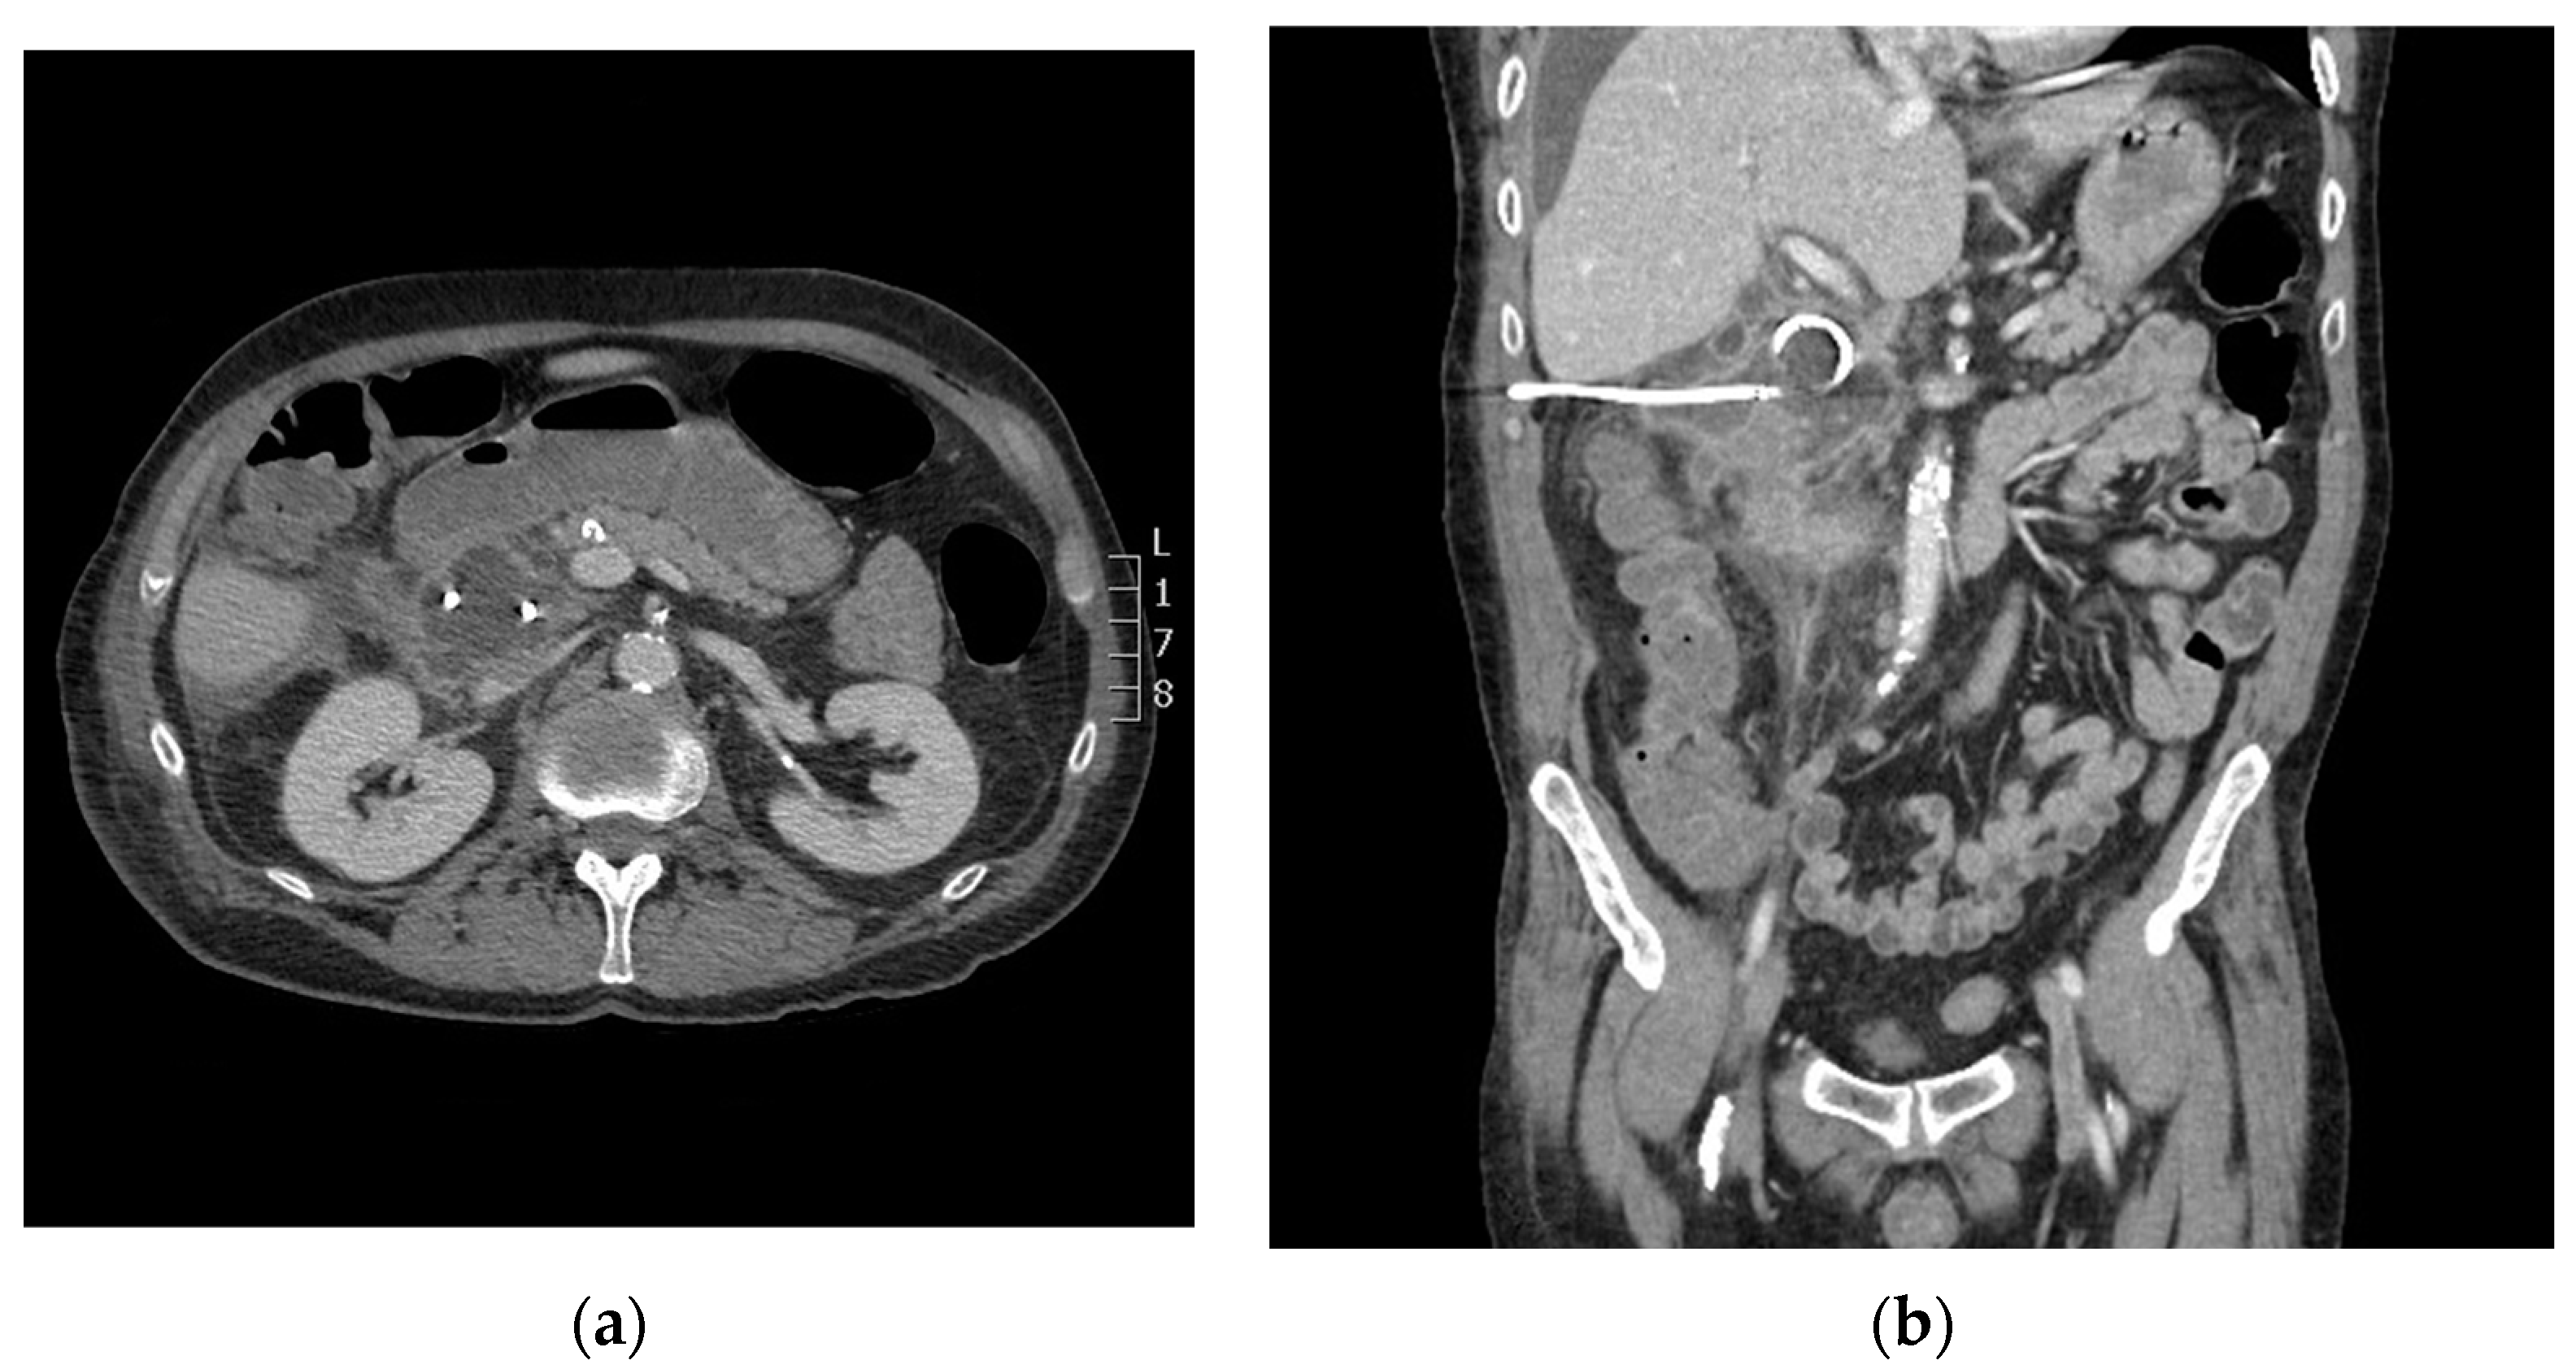

Figure 3.

Axial (a) and coronal (b) computed tomography (CT) imaging shows periduodenal drain placement with a 10 French catheter.

During the CT-guided drainage, after the needle punctured the collection and a wire was placed, the patient developed sudden onset left back pain and hypertension. CT imaging revealed a spontaneous left adrenal gland hemorrhage (Figure 2b). The drainage procedure was completed by inserting a 10 French drain over the wire and formed within the central aspect of the collection; turbid fluid was aspirated (Figure 3). After the procedure, the patient was observed in the CT suite. Intravenous (IV) analgesia was administered resulting in pain relief, and serial CT imaging with IV contrast showed stability of the left adrenal hemorrhage. Intravenous antihypertensives were administered to manage the acute hypertension. The patient was subsequently hospitalized for pain and hypertension management, secondary to spontaneous adrenal hemorrhage.